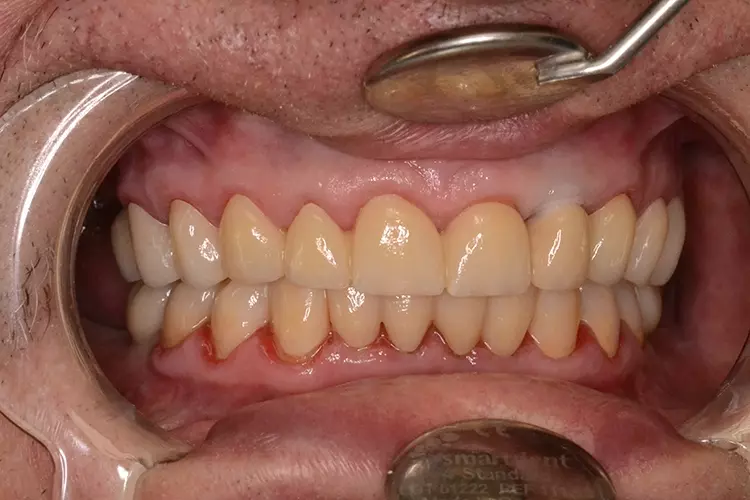

Bei dem heute 49-jährigen Patienten wurde seit Kindertagen versäumt, die Ober- und Unterkieferzahnbögen kieferorthopädisch auszurichten. Der Patient leidet seitdem stark unter seinen Zahnfehlstellungen.

Die Fraktur des stark elongierten Zahnes 21 war für den Patienten der Ausgangspunkt, sowohl die Front des Ober- als auch des Unterkiefers prothetisch überarbeiten zu lassen. Dabei wurde der frakturierte Zahn 21 durch ein navigiert eingesetztes Sofortimplantat ersetzt, während die verschachtelt stehenden Zähne 12 und 42 durch eine Brückenversorgung korrigiert wurden (Abb. 4a-j).